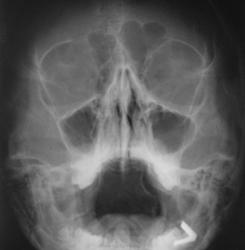

Пол пациента: Мужской пол Тип патологии: Врожденная патология Область исследования: Скелетно-мышечная система Методы исследования: Rg Юноша пришёл для исключения гайморита. Слева овальная гомогенная тень. Меня взяли сомнения по причине малого размера. Киста это или что-то ещё? ID:19251 Пнд, 27/02/2012 - 19:40 #1 Dr.Yllich Не на сайте Был на сайте: 1 год 4 месяцев назад Зарегистрирован: 01.05.2011 - 22:52 Публикации: 1196 При подобной картине пишу "Киста?" и рекомендую контроль (через 2 - 10 недель). С уважением. Ильич. Пнд, 27/02/2012 - 19:43 #2 anuta Не на сайте Был на сайте: 13 лет 9 месяцев назад Зарегистрирован: 11.10.2011 - 18:45 Публикации: 46 отправить к ЛОРам, пусть пролечат, потом на контроль Пнд, 27/02/2012 - 23:34 #3 Сан Саныч1 Не на сайте Был на сайте: 11 месяцев 3 недели назад Зарегистрирован: 07.06.2010 - 21:17 Публикации: 2114 Можно. Хочешь сделать что-то нормально - сделай это сам! Втр, 28/02/2012 - 23:23 #4 svet Не на сайте Был на сайте: 1 год 10 месяцев назад Зарегистрирован: 07.05.2010 - 19:10 Публикации: 201 отдифференцировать только рентгенологически нельзя.